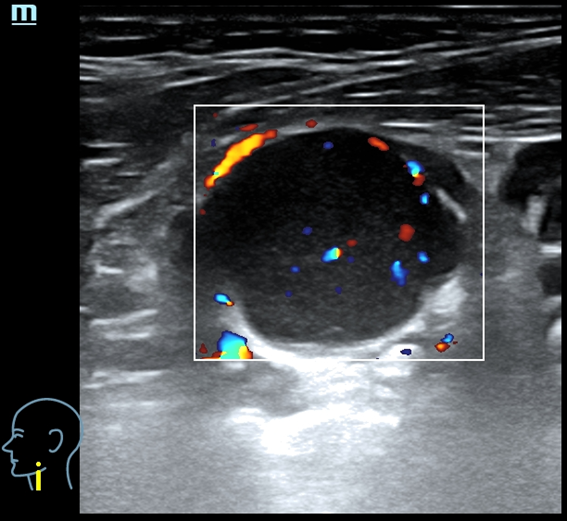

Eco clínica axilar dcha: se visualizan 3 nódulos contiguos de 4,7 x 3,39 cm y 5,4 x 2,9 cm y 5,3 x 3,9 cm. Los 3 con contornos definidos, hipoecoicos, contenido homogéneo, con refuerzo posterior, hipervascularizados,

Ante la sospecha de conglomerados de adenopatías de características tumorales se exploran ecográficamente otras zonas ganglionares visualizándose adenopatías con características tumorales (aumentadas de tamaño, redondeadas, hipoecoicas homogéneas con borramiento de hilio y vascularización cortical) en cuello, axila izquierda y región inguinal izquierda.